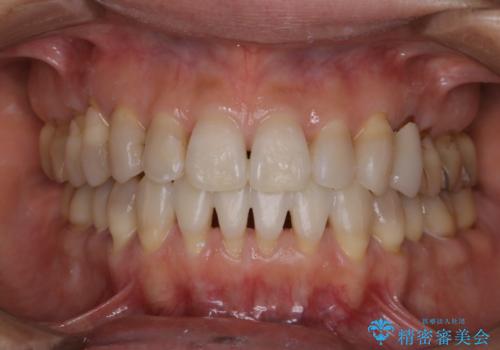

30代男性 PMTCで歯石取り

担当医 歯科衛生士